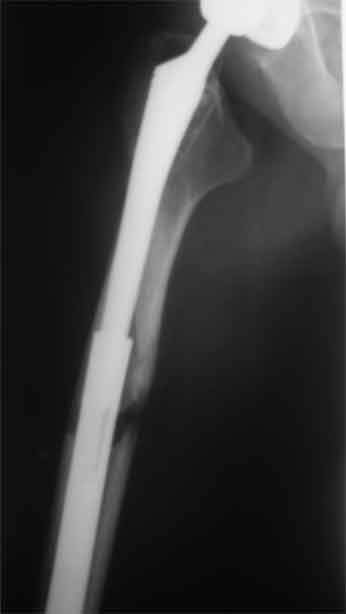

Произведено закрытое удлинение ножки эндопротеза с помощью ретроградного интрамедуллярного стержня. Продолжительность операции 3 часа. Два из них закрытое восстановление длины бедра диистрактором

А нельзя ли увидеть и профиль бедра на всем протяжении, т.е. и весь протез, и весь стержень? И фас бы с коленом.

новые снимки

Пациента удалось осмотреть недавно. Достигнутый результат сохраняется. Перелом бедра сросся. Конечность опорная и безболезненная, ходит без трости. Ножка, похоже, реинтегрировалась, как и надеялись. Снимки и фото в приложении. Комментарии приветствуются.

Надо ли что-то делать дальше, как полагаете? Убрать винты? Убрать "удлинитель ножки"? Или оставить все, как есть? Спасибо заранее.